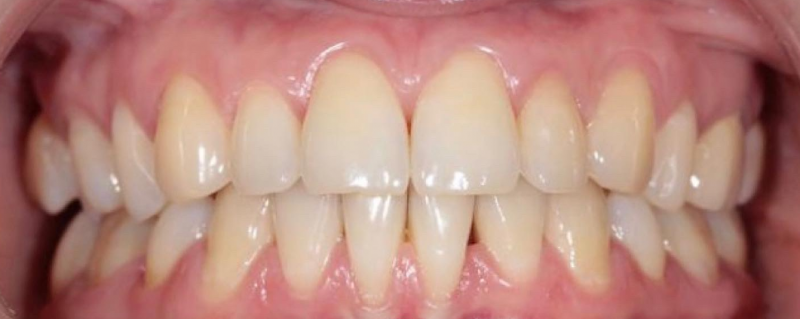

На странице представлено портфолио стоматологий Санкт-Петербурга с работами до и после профессиональной чистки зубов. В нашем портфолио собраны разные клинические случаи: от удаления незначительного налета до снятия массивного поддесневого камня. Здесь вы можете увидеть, как возвращается естественный цвет и внешний вид зубов после процедуры. Изучите результаты до и после чистки зубов, чтобы увидеть реальный эффект и выбрать клинику в Санкт-Петербурге, где профессиональная гигиена поможет вернуть зубам здоровый вид.